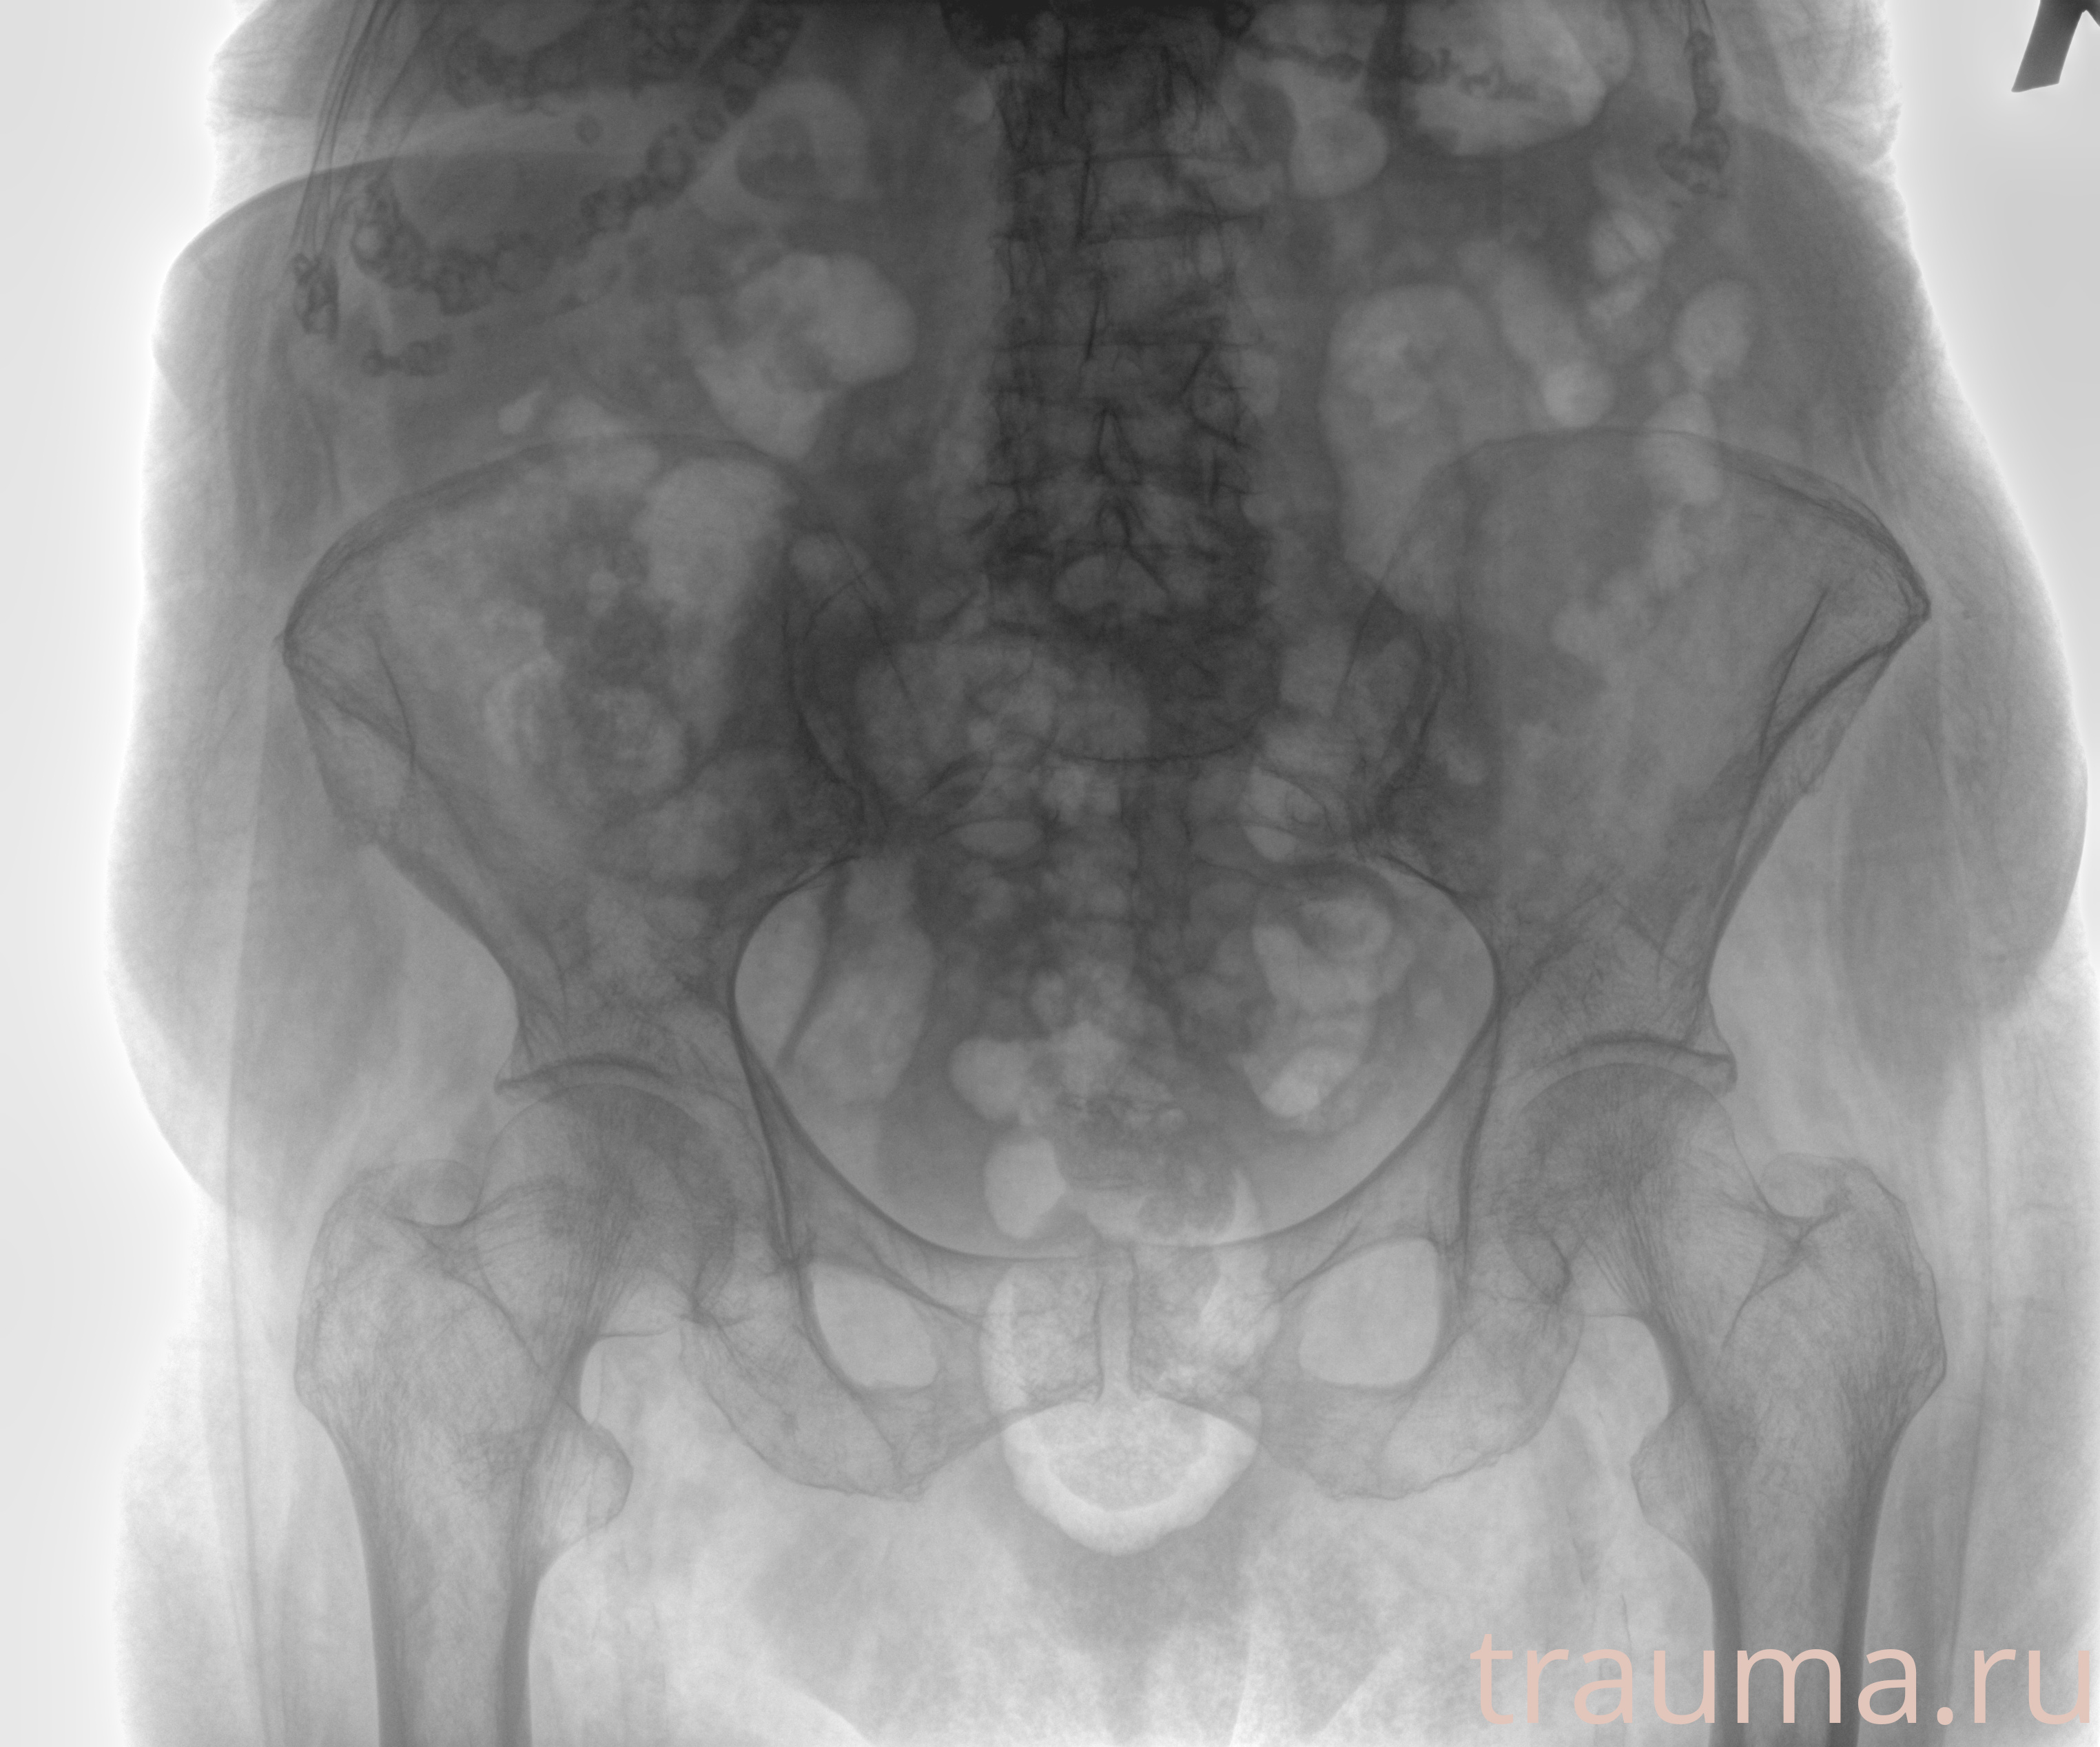

Рентген на дому: по вашему адресу приезжает врач-рентгенолог, травматолог-ортопед с мобильным рентгеновским аппаратом, проводит диагностику травмы или заболевания, делает необходимые рентгенограммы, дает рекомендации по дальнейшему лечению. Получить качественные снимки в домашних условиях возможно благодаря уникальной методике, разработанной МосРентген Центром для института  Склифосовского